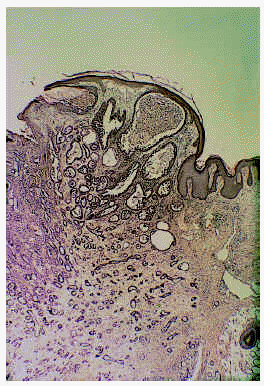

Se trata de un hombre de 26 años de edad que consultó por una lesión localizada en su axila izquierda, que no producía ningún síntoma salvo la molestia inducida por el roce, de unos 8 meses de evolución. En la exploración dermatológica se observó una tumoración eritematosa, excrecente, blanda, bien delimitada y que asentaba sobre una piel de aspecto normal (fig. 1). La lesión fue extirpada quirúrgicamente y sometida a estudio dermatopatológico. Se observó un tumor bien delimitado, con un collarete epidérmico, compuesto por múltiples estructuras tubulares, algunas de las cuales se encontraban aisladas en el seno del tumor, pero otras estaban en relación con invaginaciones epidérmicas en una zona de la lesión (fig. 2). Los túbulos se encontraban embebidos en un estroma marcadamente fibroso y tenían un diámetro muy variable, llegando a adoptar los más dilatados un aspecto quístico (fig. 3). A mayor detalle se observaba que la pared de los túbulos estaba compuesta al menos por dos capas celulares (la externa de morfología cúbica y la interna columnar); en la luz tubular existían proyecciones papilares intraluminales y secreción por decapitación y el estroma tumoral presentaba un rico infiltrado de linfocitos y células plasmáticas (figs. 4 y 5). Este cuadro clinicopatológico fue diagnosticado como ATA, aunque focalmente las imágenes histopatológicas eran indistinguibles de las de un SCAP.

Fig. 2.--Tumor exofítico compuesto por múltiples luces tubulares, algunas de las cuales contactan con invaginaciones epidérmicas remedando un siringocistoadenoma papilífero (H&E x20).

Fig. 3.--Los túbulos estaban rodeados por un estroma denso, lo cual ha inducido a plantear el término de fibroadenoma tubular apocrino para denominar esta entidad (H&E x20).

Fig. 4.--Los túbulos presentaban diámetros muy dispares y los más dilatados recordaban estructuras quísticas (H&E x40).